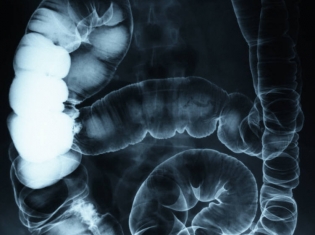

Pancreatic ductal adenocarcinoma and cytokine positive feedback

(RxWiki News) Pancreatic ductal adenocarcinoma is the worst, and unfortunately, the most common form of pancreatic cancer. Researchers are getting a grip on what makes this cancer so aggressive.